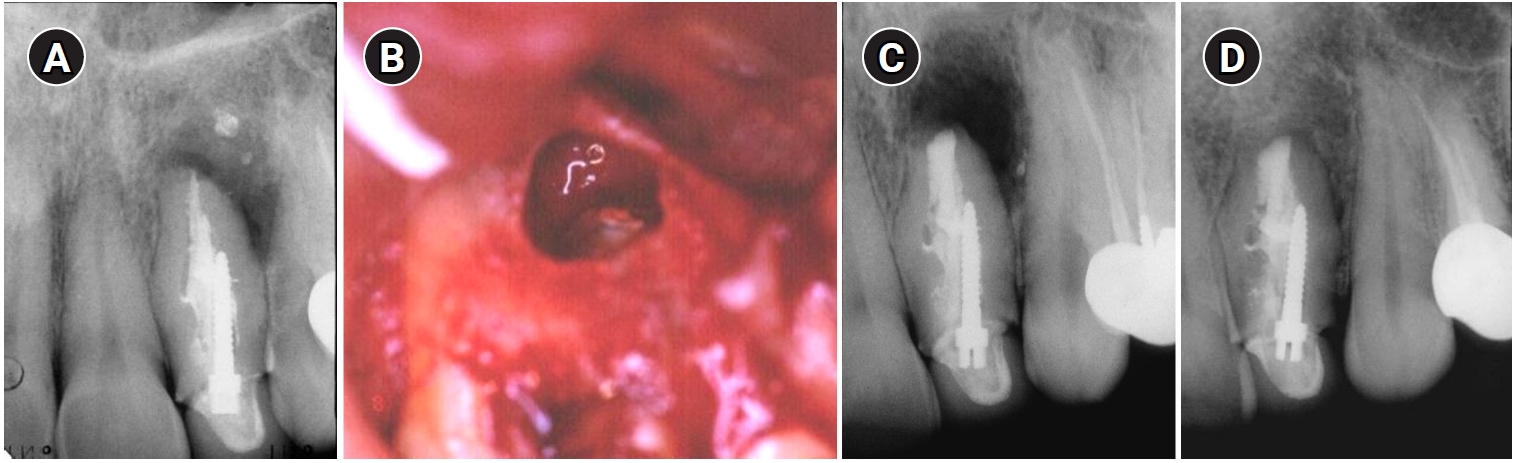

In 2011, 9 years later, the patient came back with a complaint of sensitivity in the area and purulent exudate. Clinically, the tooth was sensitive to percussion and palpation in the periapical area with signs of a sinus tract in the buccal apical area. A diagnosis of chronic apical abscess was made. A second endodontic surgery used the same technique as the previous treatment, taking care to minimize the apical resection in order not to compromise the crown-root ratio. Two years following the second surgery, the tooth was asymptomatic and completely healed radiographically (Figure 3).

Endodontic reoperation on tooth #22. (A) Preoperative radiograph in 2011. (B) Postoperative radiograph in 2011 showing minimal apical resection. (C) Two-year follow-up radiograph in 2012 showing complete healing with normal periodontal ligament space.

Figure 3. Endodontic reoperation on tooth #22. (A) Preoperative radiograph in 2011. (B) Postoperative radiograph in 2011 showing minimal apical resection. (C) Two-year follow-up radiograph in 2012 showing complete healing with normal periodontal ligament space.